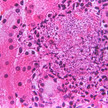

Darmerkrankungen Morbus Crohn: Onkogen Bcl-3 als Auslöser

Krampfartige Bauchschmerzen und wässrige Durchfälle in Schüben können die Symptome von Morbus Crohn sein. Die Ursachen der entzündlichen Darmerkrankung sind... Mehr»